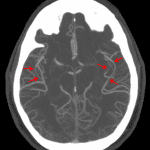

- Multifocal areas of mild luminal narrowing/irregularity of bilateral M2 and M3 middle cerebral artery branches

- Reversible cerebral vasoconstriction syndrome (RCVS)

No evidence of arterial occlusion or aneurysm. No CT evidence of acute ischemia or hemorrhage.

Multifocal areas of mild luminal narrowing/irregularity of bilateral M2 and M3 middle cerebral artery branches which though nonspecific can be seen in the setting of vasculopathy, including reversible cerebral vasoconstriction syndrome (RCVS).